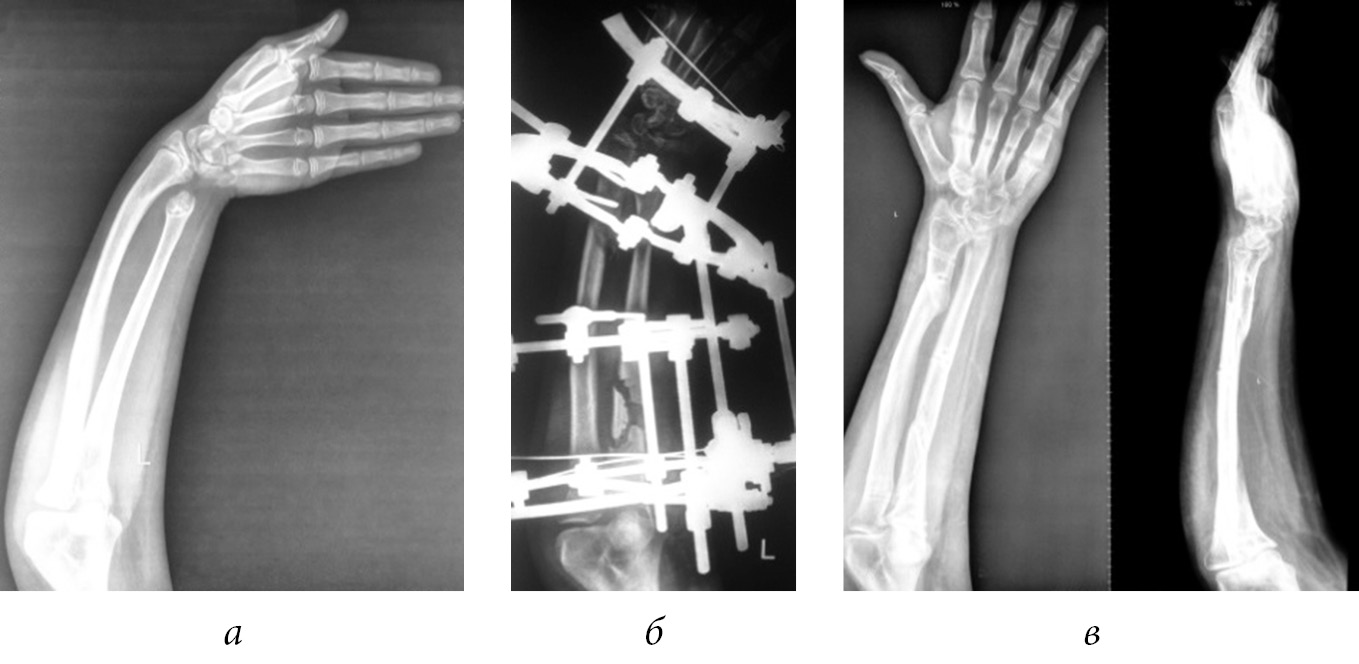

We believe that elimination of deformity of only a shortened bone is not enough, since in the process of child growth, the adjacent forearm bone is deformed, causing pronounced cosmetic and functional disorders (Fig. 5).

Fig. 5. Radiographs of the left forearm of patient G. before (a), in the process (b), and after (c) the elimination of the ulnar clubhand